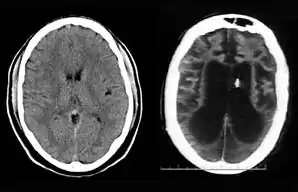

On August 10, 2001, on remand from the Florida Second District Court of Appeal, Judge Greer heard a motion from the Schindlers claiming that new medical treatment could restore sufficient cognitive ability such that Terri Schiavo herself would be able to decide to continue life-prolonging measures. The court also heard motions from the Schindlers to remove the guardian (Michael Schiavo) and to require Judge Greer to recuse himself. Judge Greer denied the motions and the Schindlers appealed to the Second District Court of Appeals. On October 17, 2001, the Court of Appeal affirmed the denials of the motions to remove and recuse. The Court of Appeals acknowledged that their opinion misled the trial court, and they remanded the question of Terri Schiavo's wishes back to the trial court and required an evidentiary hearing to be held. The court specified that five board certified neurologists were to testify. The Schindlers were allowed to choose two doctors to present findings at an evidentiary hearing while Schiavo could introduce two rebuttal experts. Finally, the trial court itself would appoint a new independent physician to examine and evaluate Terri Schiavo's condition. (These decisions, all published in a single order by the Florida Second District Court of Appeal,[34] came to be known by the court as Schiavo III in its later rulings.) In October 2002, on remand by the Second District Court of Appeal, an evidentiary hearing was held in Judge Greer's court to determine whether new therapy treatments could help Terri Schiavo restore any cognitive function. In preparation for the trial, a new computed axial tomography scan (CAT scan) was performed, which showed severe cerebral atrophy. An EEG showed no measurable brain activity. The five physicians chosen were William Maxfield, a radiologist, and four neurologists: William Hammesfahr, Ronald Cranford, Melvin Greer and Peter Bambakidis.[35]

The five doctors examined Terri Schiavo's medical records, brain scans, the videos, and Terri herself. Cranford, Greer, and Bambakidis testified that Terri Schiavo was in a persistent vegetative state (PVS). Drs. Maxfield and Hammesfahr testified that she was in a minimally conscious state. As part of the court-ordered medical exam, six hours of video of Terri Schiavo were taped and filed at the Pinellas County courthouse. The tape included Terri Schiavo with her mother and neurologist William Hammesfahr. The entire tape was viewed by Judge Greer, who wrote, Terri "clearly does not consistently respond to her mother". From that six hours of video, the Schindlers and their supporters produced six video clips intended to support their case, totaling less than six minutes, and released those clips to public websites.[1] Judge Greer ruled that Terri Schiavo was in a PVS, and was beyond hope of significant improvement. The trial court order was particularly critical of Hammesfahr's testimony, which claimed positive results in similar cases by use of vasodilation therapy, the success of which is unsupported in the medical literature.[36] This ruling was later affirmed by Florida's Second District Court of Appeal, which stated that "this court has closely examined all of the evidence in the record", and "we have ... carefully observed the video tapes in their entirety." The court concluded that "if we were called upon to review the guardianship court's decision de novo, we would still affirm it." This decision by the Second District Court of Appeals[37] came to be known as Schiavo IV in later rulings.

Schiavo's body was taken to the Office of the District 6 Medical Examiner for Pinellas and Pasco counties, based in Largo, Florida. The autopsy was conducted on April 1, 2005, and revealed extensive brain damage. The manner of death was certified as "undetermined." The autopsy was led by Chief Medical Examiner Jon R. Thogmartin. In addition to consultation with a neuropathologist (Stephen J. Nelson), Thogmartin also arranged for specialized cardiac and genetic examinations to be made. The official autopsy report[29] was released on June 15, 2005. In addition to studying Terri Schiavo's remains, Thogmartin scoured court, medical and other records and interviewed her family members, doctors and other relevant parties. Examination of Schiavo's nervous system by neuropathologist Stephen J. Nelson, revealed extensive injury. The brain itself weighed only 615 g (21.7 oz), only half the weight expected for a female of her age, height, and weight, due to the loss of a massive number of neurons. Microscopic examination revealed extensive damage to nearly all brain regions, including the cerebral cortex, the thalamus, the basal ganglia, the hippocampus, the cerebellum, and the midbrain. The neuropathologic changes in her brain were precisely of the type seen in patients who enter a PVS following cardiac arrest. Throughout the cerebral cortex, the large pyramidal neurons that comprise some 70% of cortical cells – critical to the functioning of the cortex – were completely lost. The pattern of damage to the cortex, with injury tending to worsen from the front of the cortex to the back, was also typical. There was marked damage to important relay circuits deep in the brain (the thalamus) – another common pathologic finding in cases of PVS. The damage was, in the words of Thogmartin, "irreversible, and no amount of therapy or treatment would have regenerated the massive loss of neurons."[67]